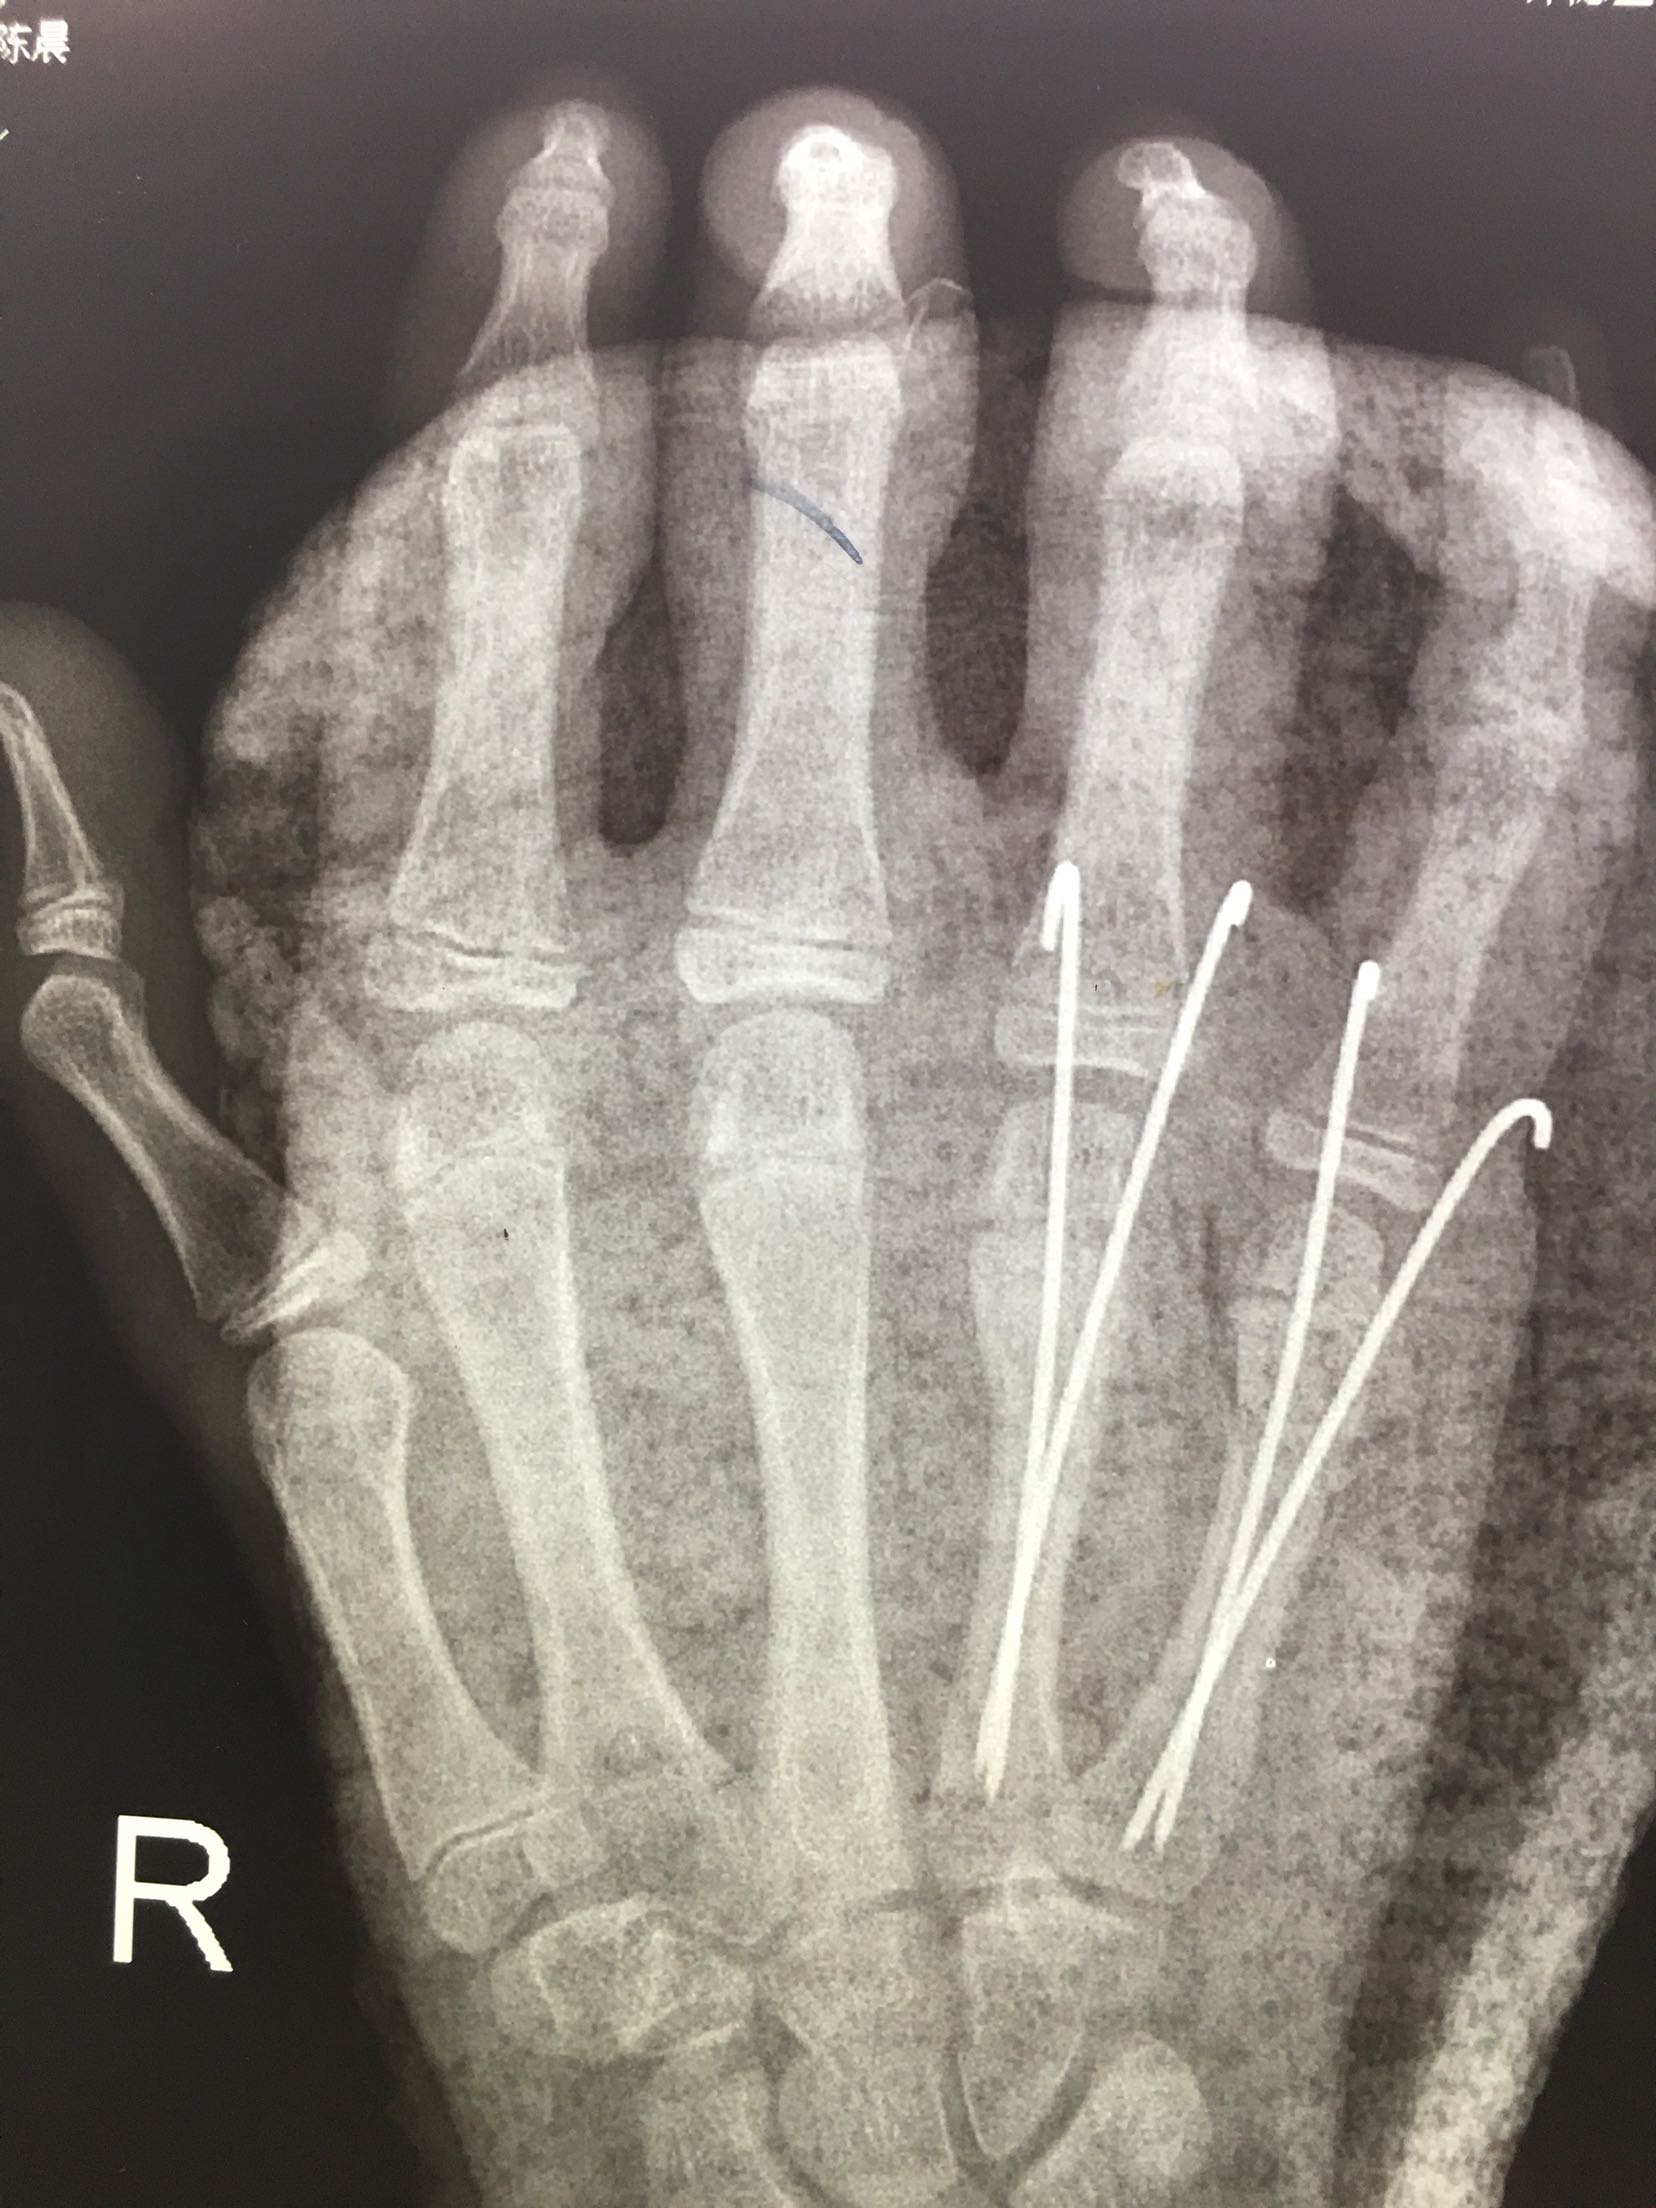

右第四,五掌骨骨折(微创)

完善检查,在臂丛麻醉下行闭合复位内固定术,术后抗炎,消肿止痛等对症处理,右手石膏托制动。